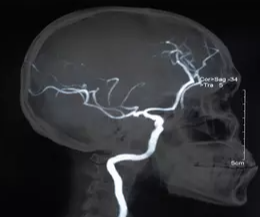

뇌졸중은 뇌로 가는 혈관이 막히거나 터져 뇌세포가 손상되는 급성 질환입니다. 뇌는 우리 몸의 모든 기능을 조절하는 중추 기관이기 때문에, 사망률과 장애율이 매우 높은 치명적인 질환입니다. 우리나라에서는 흔히 '중풍'이라고도 불립니다.

뇌혈관이 막혀 뇌로 가는 혈액 공급이 차단되는 경우입니다. 뇌졸중의 약 85%가 허혈성 뇌졸중입니다. 뇌경색 이라고도 불립니다.

뇌혈관이 파열되어 뇌 안이나 주변에 혈액이 새는 경우입니다. 뇌졸중의 약 15%가 출혈성 뇌졸중입니다. 뇌출혈 이라고도 불립니다.